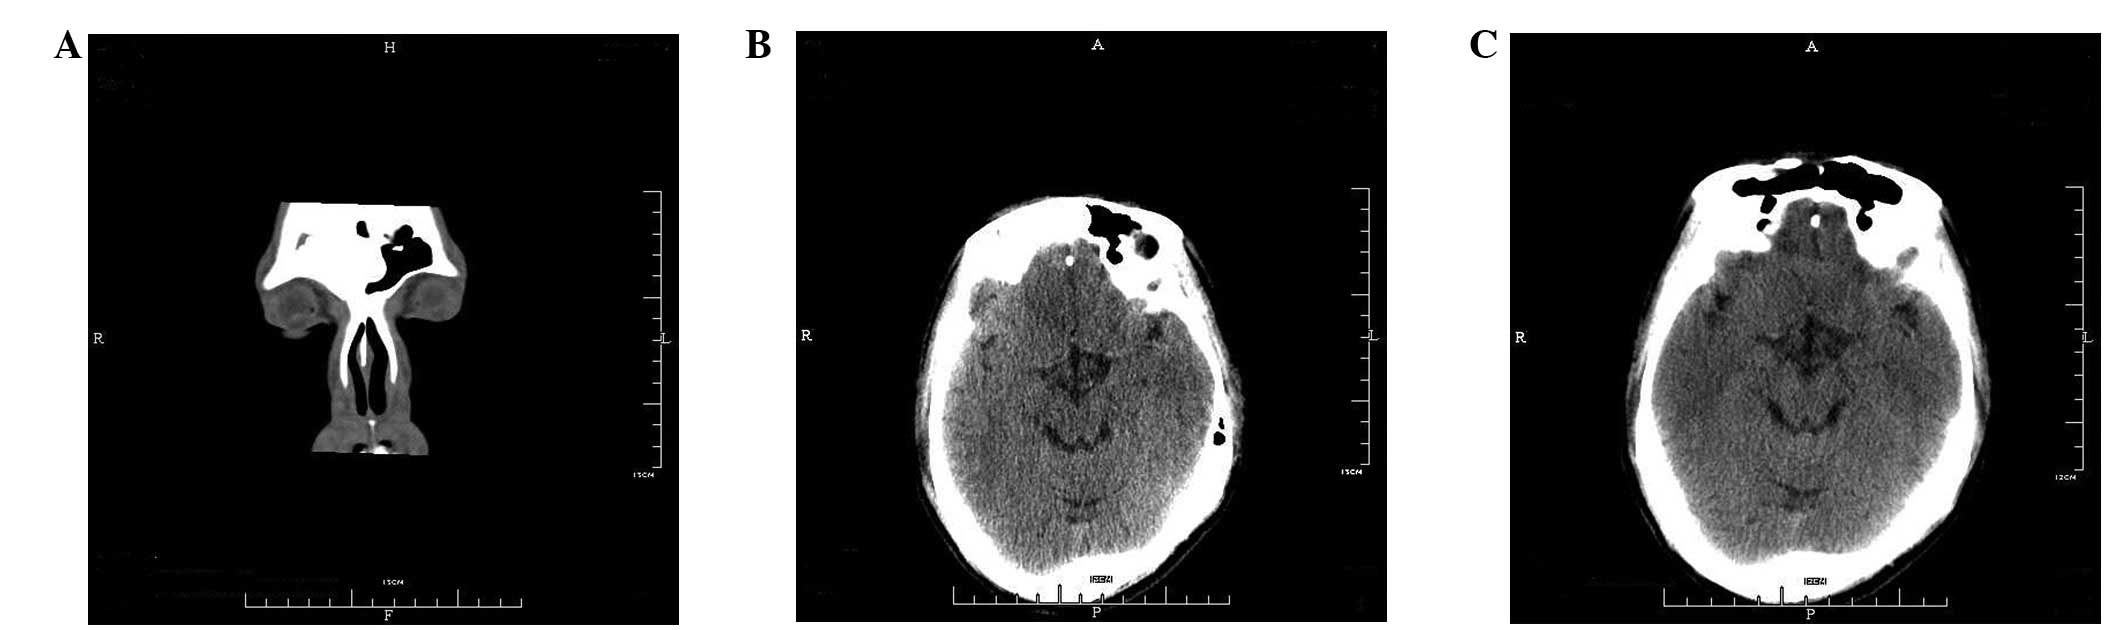

Giant osteomas of the ethmoid and frontal sinuses: Clinical characteristics and review of the literature

Giant osteomas of the ethmoid and frontal sinuses ary very rare, with only a few dozen cases reported in the literature. Given their rarity, the clinical characteristics and treatment of this disease remain controversial. In this study, the clinical presentation and surgical methods used to treat three patients with giant osteomas of the ethmoid and frontal sinuses are described, combined with a review of the literature from 1975 to 2011. In total, 45 patients with giant osteomas arising from the ethmoid and frontal sinuses (including the present cases) have been reported in 41 articles. Headache and ocular signs are the most common symptoms. This disease often leads to intracranial or intraorbital complications. The main treatment for giant osteoma is surgery via an external approach. The outcome of surgery for giant osteoma is good, with rare recurrence, no malignant transformation and few persistent symptoms.

Figure 1

Figure 2

Figure 3